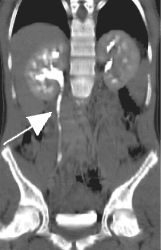

Left image is a pre-contrast transverse image showing a 3 mm calculus (arrow) in the region of the right ureter anterior to the psoas muscle.